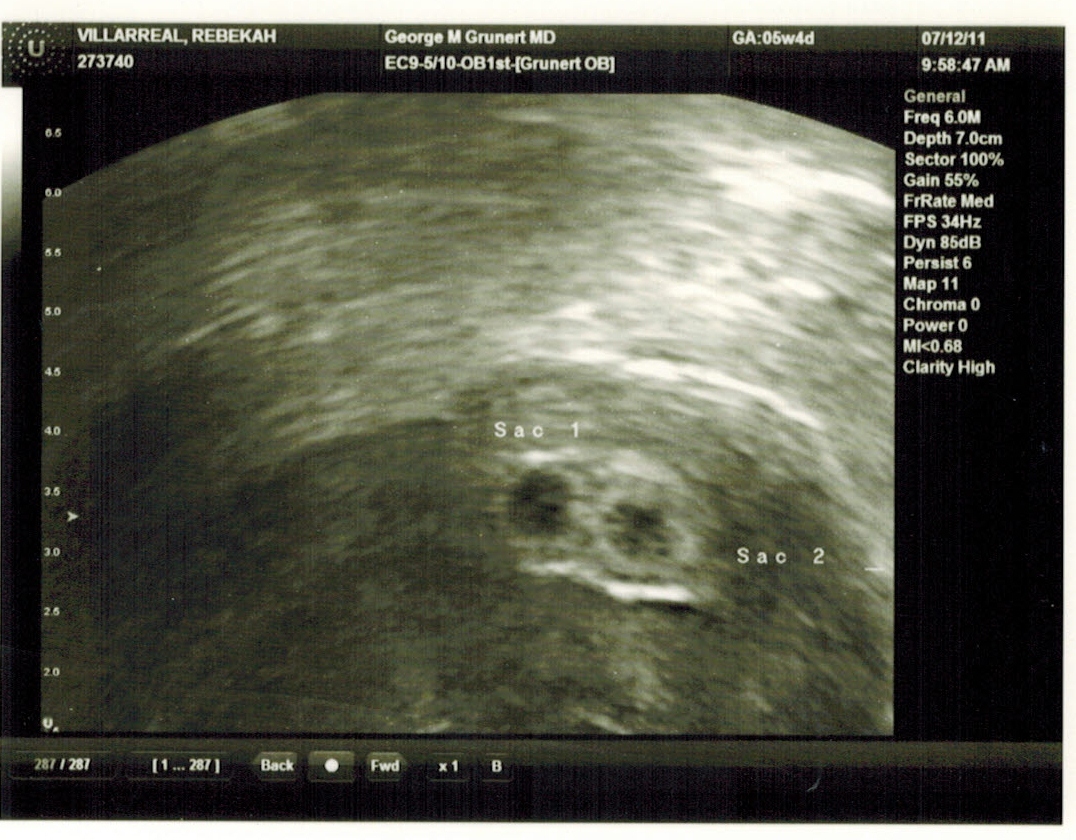

Twins First Image